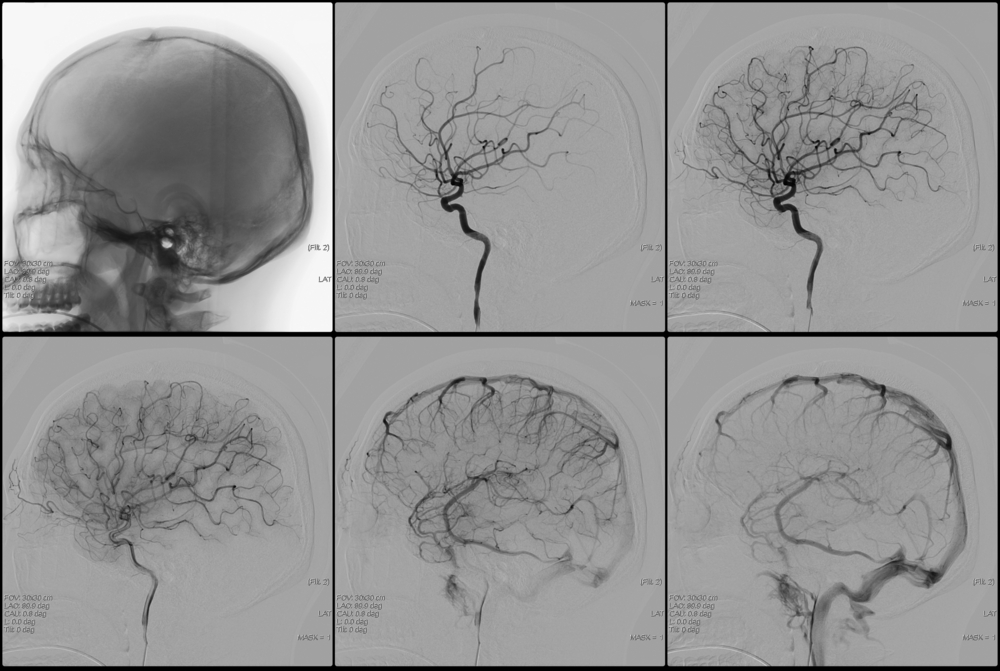

Суть этого метода исследования заключается в следующем. Больному в определенную артерию головного мозга (или всю сеть артерий мозга) вводится рентгенконтрастное вещество, обычно на основе йода (Урографин, Трийодтраст, Омнипак, Ультравист и другие). Это делается для того, чтобы можно было на рентгеновской пленке зафиксировать изображение сосуда, поскольку при обычном снимке сосуды плохо визуализируются. Введение рентгенконтрастного вещества возможно путем пункции соответствующего сосуда (если это технически выполнимо) либо через катетер, подведенный к необходимому сосуду с периферии (обычно из бедренной артерии). Когда контрастное вещество оказывается в сосудистом русле, производится серия рентгеновских снимков в двух проекциях (прямой и боковой). Полученные снимки оцениваются врачом-рентгенологом, им делаются выводы о наличии либо отсутствии определенной патологии сосудов головного мозга.

Пациент укладывается на стол и подключается к приборам (кардиомонитор, пульсоксиметр). После обработки кожи местным анестетиком и обезболивания производится прокол соответствующего сосуда (сонной или позвоночной артерии). Поскольку точно попасть в эти артерии не всегда возможно, то чаще всего осуществляется небольшой разрез кожи и прокол бедренной артерии с последующим погружением катетера и проведением его по сосудам к месту исследования. Продвижение катетера по артериальному руслу не сопровождается болью, поскольку внутренняя стенка сосудов лишена болевых рецепторов. Контроль продвижения катетера производят с помощью рентгена. Когда катетер будет подведен к устью необходимого сосуда, через него вводится предварительно подогретый до температуры тела контрастный препарат в объеме 8-10 мл. Введение контраста может сопровождаться появлением металлического привкуса во рту, чувством жара, прилива крови к лицу. Эти ощущения самостоятельно проходят в течение нескольких минут. После введения контраста производятся рентгеновские снимки в прямой и боковой проекциях почти каждую секунду несколько раз (что позволяет увидеть и артерии, и капиллярную фазу, и вены). Снимки проявляют и сразу оценивают. Если что-то осталось непонятным для врача, вводится дополнительная порция контрастного вещества, и снимки повторяют. Затем катетер удаляют, на место пункции сосуда накладывают давящую стерильную повязку. За пациентом должен наблюдать медицинский персонал как минимум в течение 6-10 часов.